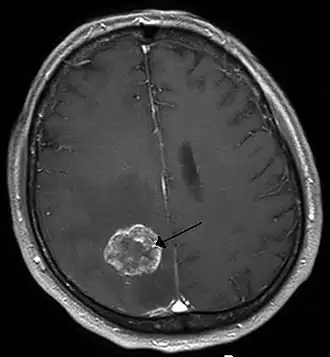

Опухоль головного мозга

Опухоль головного мозга. Визуализируется с помощью МРТ. | |

К обязательным методам обследования относятся определение активности сухожильных рефлексов, проверка тактильной и болевой чувствительности. Диагностические мероприятия могут быть расширены в зависимости от жалоб больного и с целью дифференциальной диагностики. Так, например, если больной отмечает нарушения координации, следует провести пальце-носовую пробу, проверить устойчивость в позе Ромберга. Если возникает подозрение на опухоль мозга, то больной направляется на компьютерную (КТ) или магнитно-резонансную томографию (МРТ). МРТ с контрастным усилением является «золотым стандартом» в диагностике опухолей головного мозга[6]. При обнаружении на томограмме объёмного образования решается вопрос о госпитализации больного в специализированный стационар.